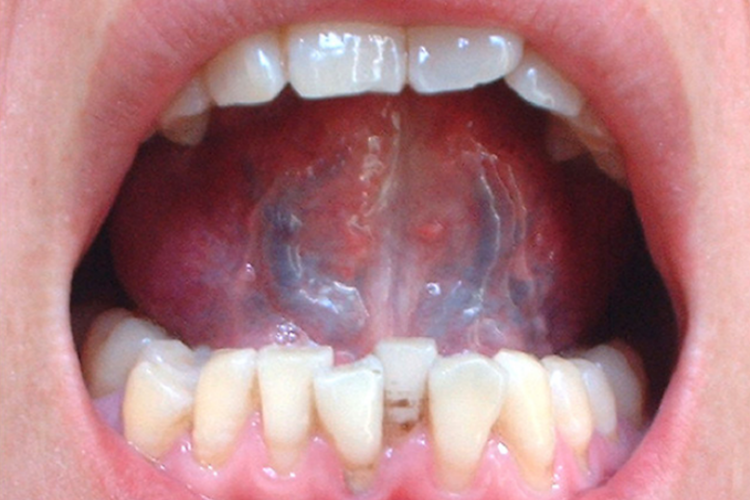

舌下静脉瘀堵四级表现为舌下络脉主干饱满,曲张明显,直径>2.7mm,颜色紫黑。

舌下络脉可分为正常、异常Ⅰ度、异常Ⅱ度、异常Ⅲ度。舌下静脉瘀堵四级即异常Ⅲ度,表现为舌下络脉主干饱满,曲张明显,直径>2.7mm,长度超过舌系带止点与舌尖的3/5或将及尖,颜色紫黑,外带有粗枝状分支或鱼子酱剌。